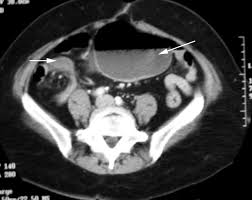

The patients symptoms resolved quickly after colonoscopic reduction and elective laparoscopic surgery was performed 18 days after admission. A planned surgery is not fun but an emergency surgery for a twisted colon would be even worse. Based on these findings we diagnosed cecal volvulus caused by mobile cecum syndrome. On the other hand a chronic form of mobile cecum syndrome which is the most common form reported a history of intermittent crampy abdominal pain distension and constipation. However it may be present as a precursor of frank cecal volvulus in approximately 50 per cent of the cases. 102 patients were followed up to 15 years after the operation. Abstract Five cases of mobile cecum syndrome are presented. Ehlers-Danlos syndrome hypermobility type EDS-HT mobile cecum ptosis laparoscopic. The following symptoms may be experienced with cecal volvulus.

On the other hand a chronic form of mobile cecum syndrome which is the most common form reported a history of intermittent crampy abdominal pain distension and constipation. It lies at the junction of the small and the large intestines and is the origin of the appendix. Ballooning abdomen abdominal distension. Thats about as mobile as you can get. The following symptoms may be experienced with cecal volvulus. A mobile caecum and ascending colon is a rare congenital abnormality. The cecal volvulus represents the acute form with typical feature of a bowel obstruction that needs immediate operative treatment.